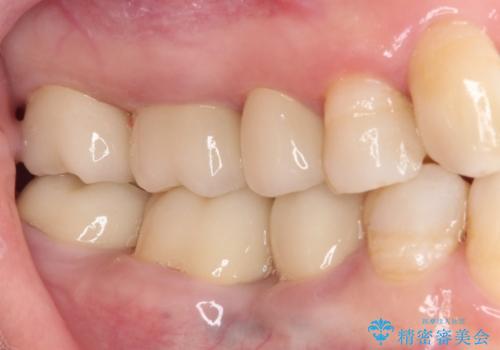

矯正治療後にはオールセラミッククラウンにて補綴治療を行うこととしました。

歯冠長延長術を行ったことで、自然な形態かつ清掃性の高いセラミッククラウンを装着することができました。

全顎的に治療を行ったため、治療期間も費用も負担は大きくなりましたが、統一感のある仕上がりとなりました。